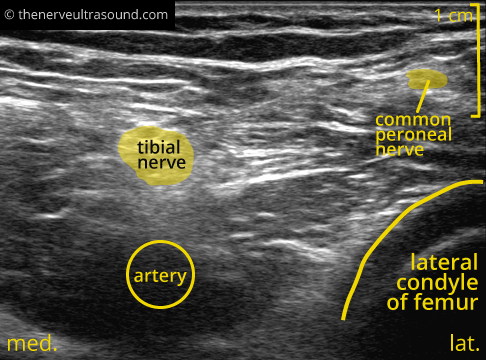

At the popliteal fossa the main branches of the sciatic nerve are visible. The tibial nerve lies superficial

to the popliteal artery. Especially in individuals with difficult sonoanatomy it may be easier to start the scanning of the distal course of the sciatic nerve at this level; positioning of the probe in the popliteal fossa, looking for the pulsation of the artery, focusing superficial to the artery looking for the “appearance” of

a hyperechogenic structure whilst tilting the ulrasound-probe; the tibial nerve. When the tibial nerve is identified, tracking it proximally till the union with the common peroneal nerve from lateral – the bifurcation of the sciatic nerve is identified.

Another possibility is the identification of the common peroneal nerve on the fibular neck and tracking it back proximal up to the bifurcation.